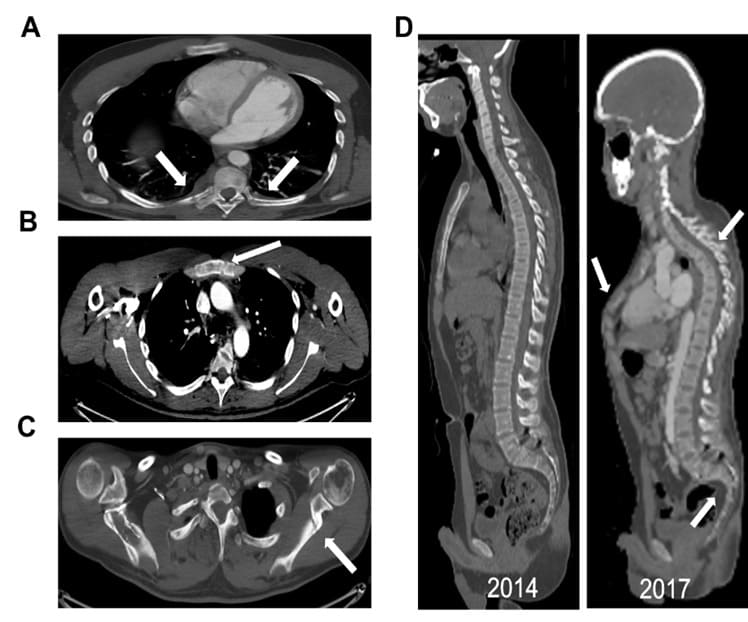

A 28-year-old otherwise healthy male, developed skeletal, muscular and joints pain 5 years’ prior to his arrival to our institution. The patient had no history of smoking, ethanol intake, antiseizure medication, antacid abuse, steroid use, bisphosphonates or antidiabetic medications. Due to severe low back pain, the patient was diagnosed with L5-S1 bilateral spondylolisthesis and treated with bilateral pedicle screw hook fixation (Figure 1). In spite of the treatment, the patient continued to deteriorate, he became bedridden due to severe pain and fatigue, until his referral to our institution. Upon his arrival, the radiological survey revealed a convex deformity of both his hips with subcapital fracture of the right femur (Figure 1), multiple rib and vertebrae fractures (Figure 2A), fracture of the left scapula (Figure 2B), fracture of the sternum (Figure 2C), severe pectus carinatum with thoracic and sacral kyphosis (Figure 2D). A DXA study showed severe osteoporosis (T score <-2.5) [10]. Biochemical investigations revealed a low serum phosphorus level (1.1 mg/dL) and an elevated alkaline phosphatase level (287 u/l). Serum creatinine, calcium, and albumin were found to be normal. Serum 1,25-dihydroxyvitamin D level was low (10.1pg/ml). This data led to the suspicion of TIO. As a result, we evaluated the levels of FGF23 in the blood. The plasma FGF23 levels were collected from the right and left median cubital veins and from the femoral veins and showed levels of 1802 pg/ml, 1816 pg/ml, 2319 pg/ml, and 1806 pg/ml, respectively (normal reference range: 23.2 – 95.4 pg/ml). A 68GA-DOTATATE PET/CT scan demonstrated uptake in a 2.5 cm x 1.6 cm lesion located in the right popliteal fossa. The patient was referred to the orthopedic oncology surgical unit with the diagnosis of a possible phosphaturic mesenchymal tumor. After clinical evaluation of the tumor, MRI and CT studies with contrast injection of the right knee were performed. The studies demonstrated a soft tissue lesion in the right popliteal fossa, 2.3 cm in diameter, located adjacent to the popliteal vessels, the tibial nerve and the common peroneal nerve (Figure 3). Once the dimensions and the borders of the lesion were defined and confirmed, surgical treatment was recommended. A wide resection of the tumor was performed. Histopathological examination disclosed a mesenchymal tumor, composed of spindle cells and osteoclast-like giant cells, with free surgical margins. 14 hours post-surgery, blood samples presented a normal FGF23 level (52.67 pg/ml). One-week post-surgery, the levels of serum phosphorus also returned to normal (Figure 4).

Figure 2: A. Axial CT demonstrating fractures (looser zones) of the posterior aspects of bilateral ribs. B. Axial CT demonstrating fracture (looser zone) of the manubrium sterni. C. Axial CT demonstrating fracture (looser zone) of the left scapula. D. Sagittal CT demonstrating dynamic changes and appearance of severe pectus carinatum with thoracic and sacral kyphosis.